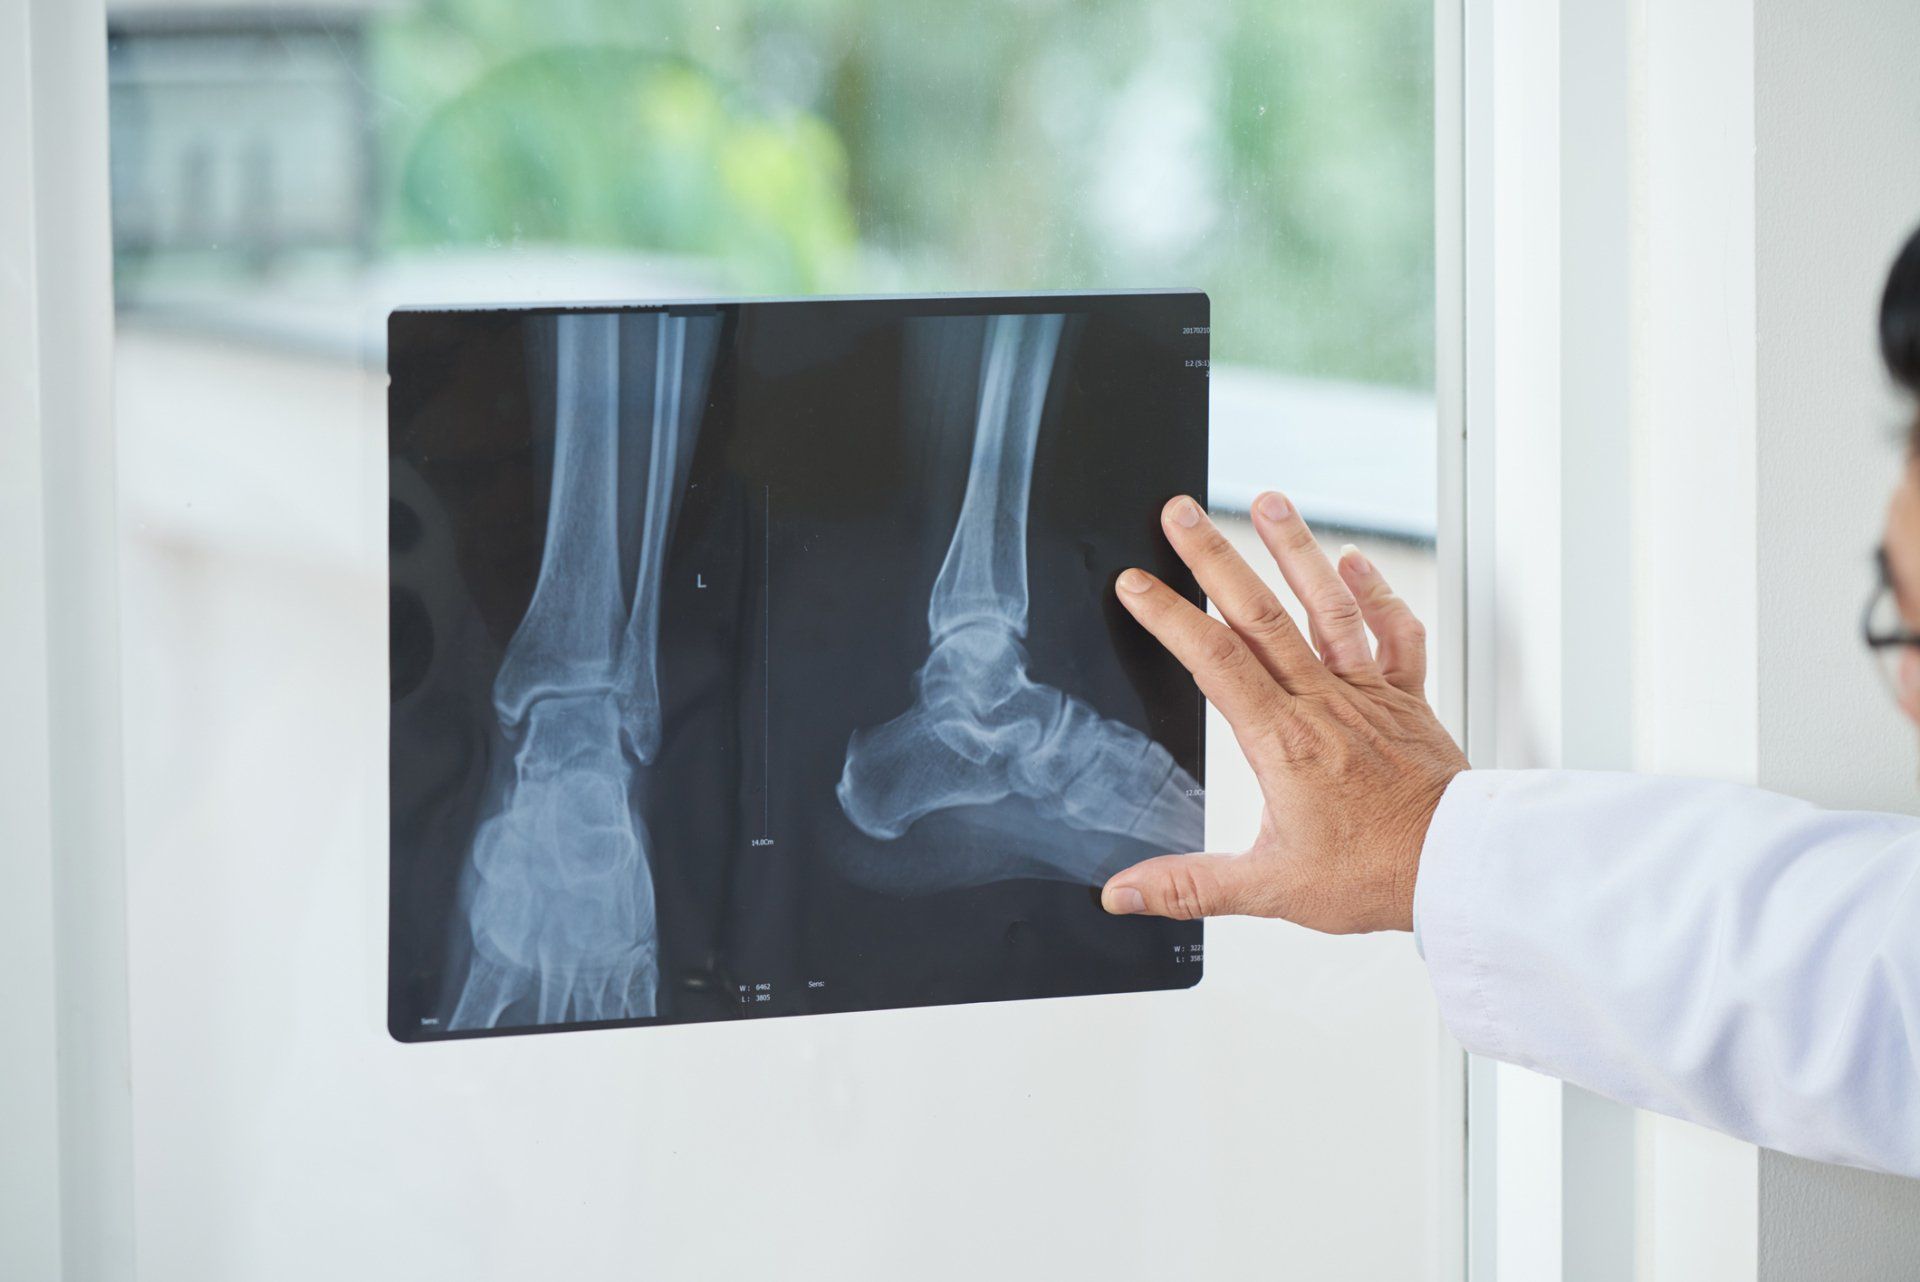

Foot and ankle specialists confirm the diagnosis with history of injury and thorough physical examination. In some cases, additional imaging (such as MRI or XRs) are necessary to provide more information about the location of tear or integrity of the soft tissues.